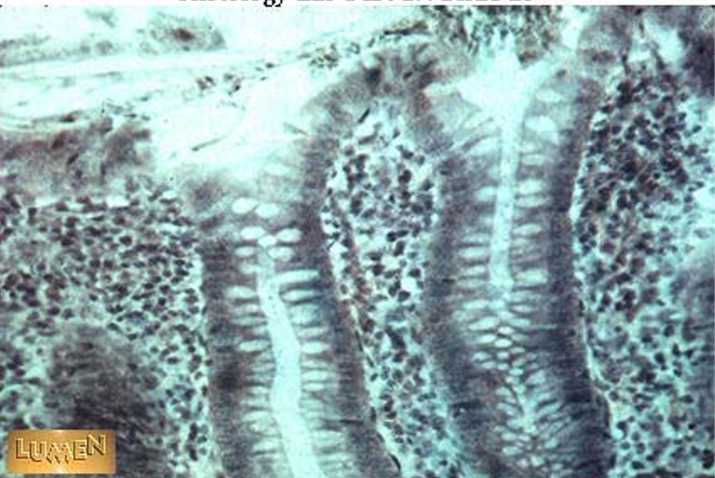

the arrows point to

brush border/microvilli

villi

the blue arrow

the red arrow

the black arrows

crypts

this is in the

jejunum